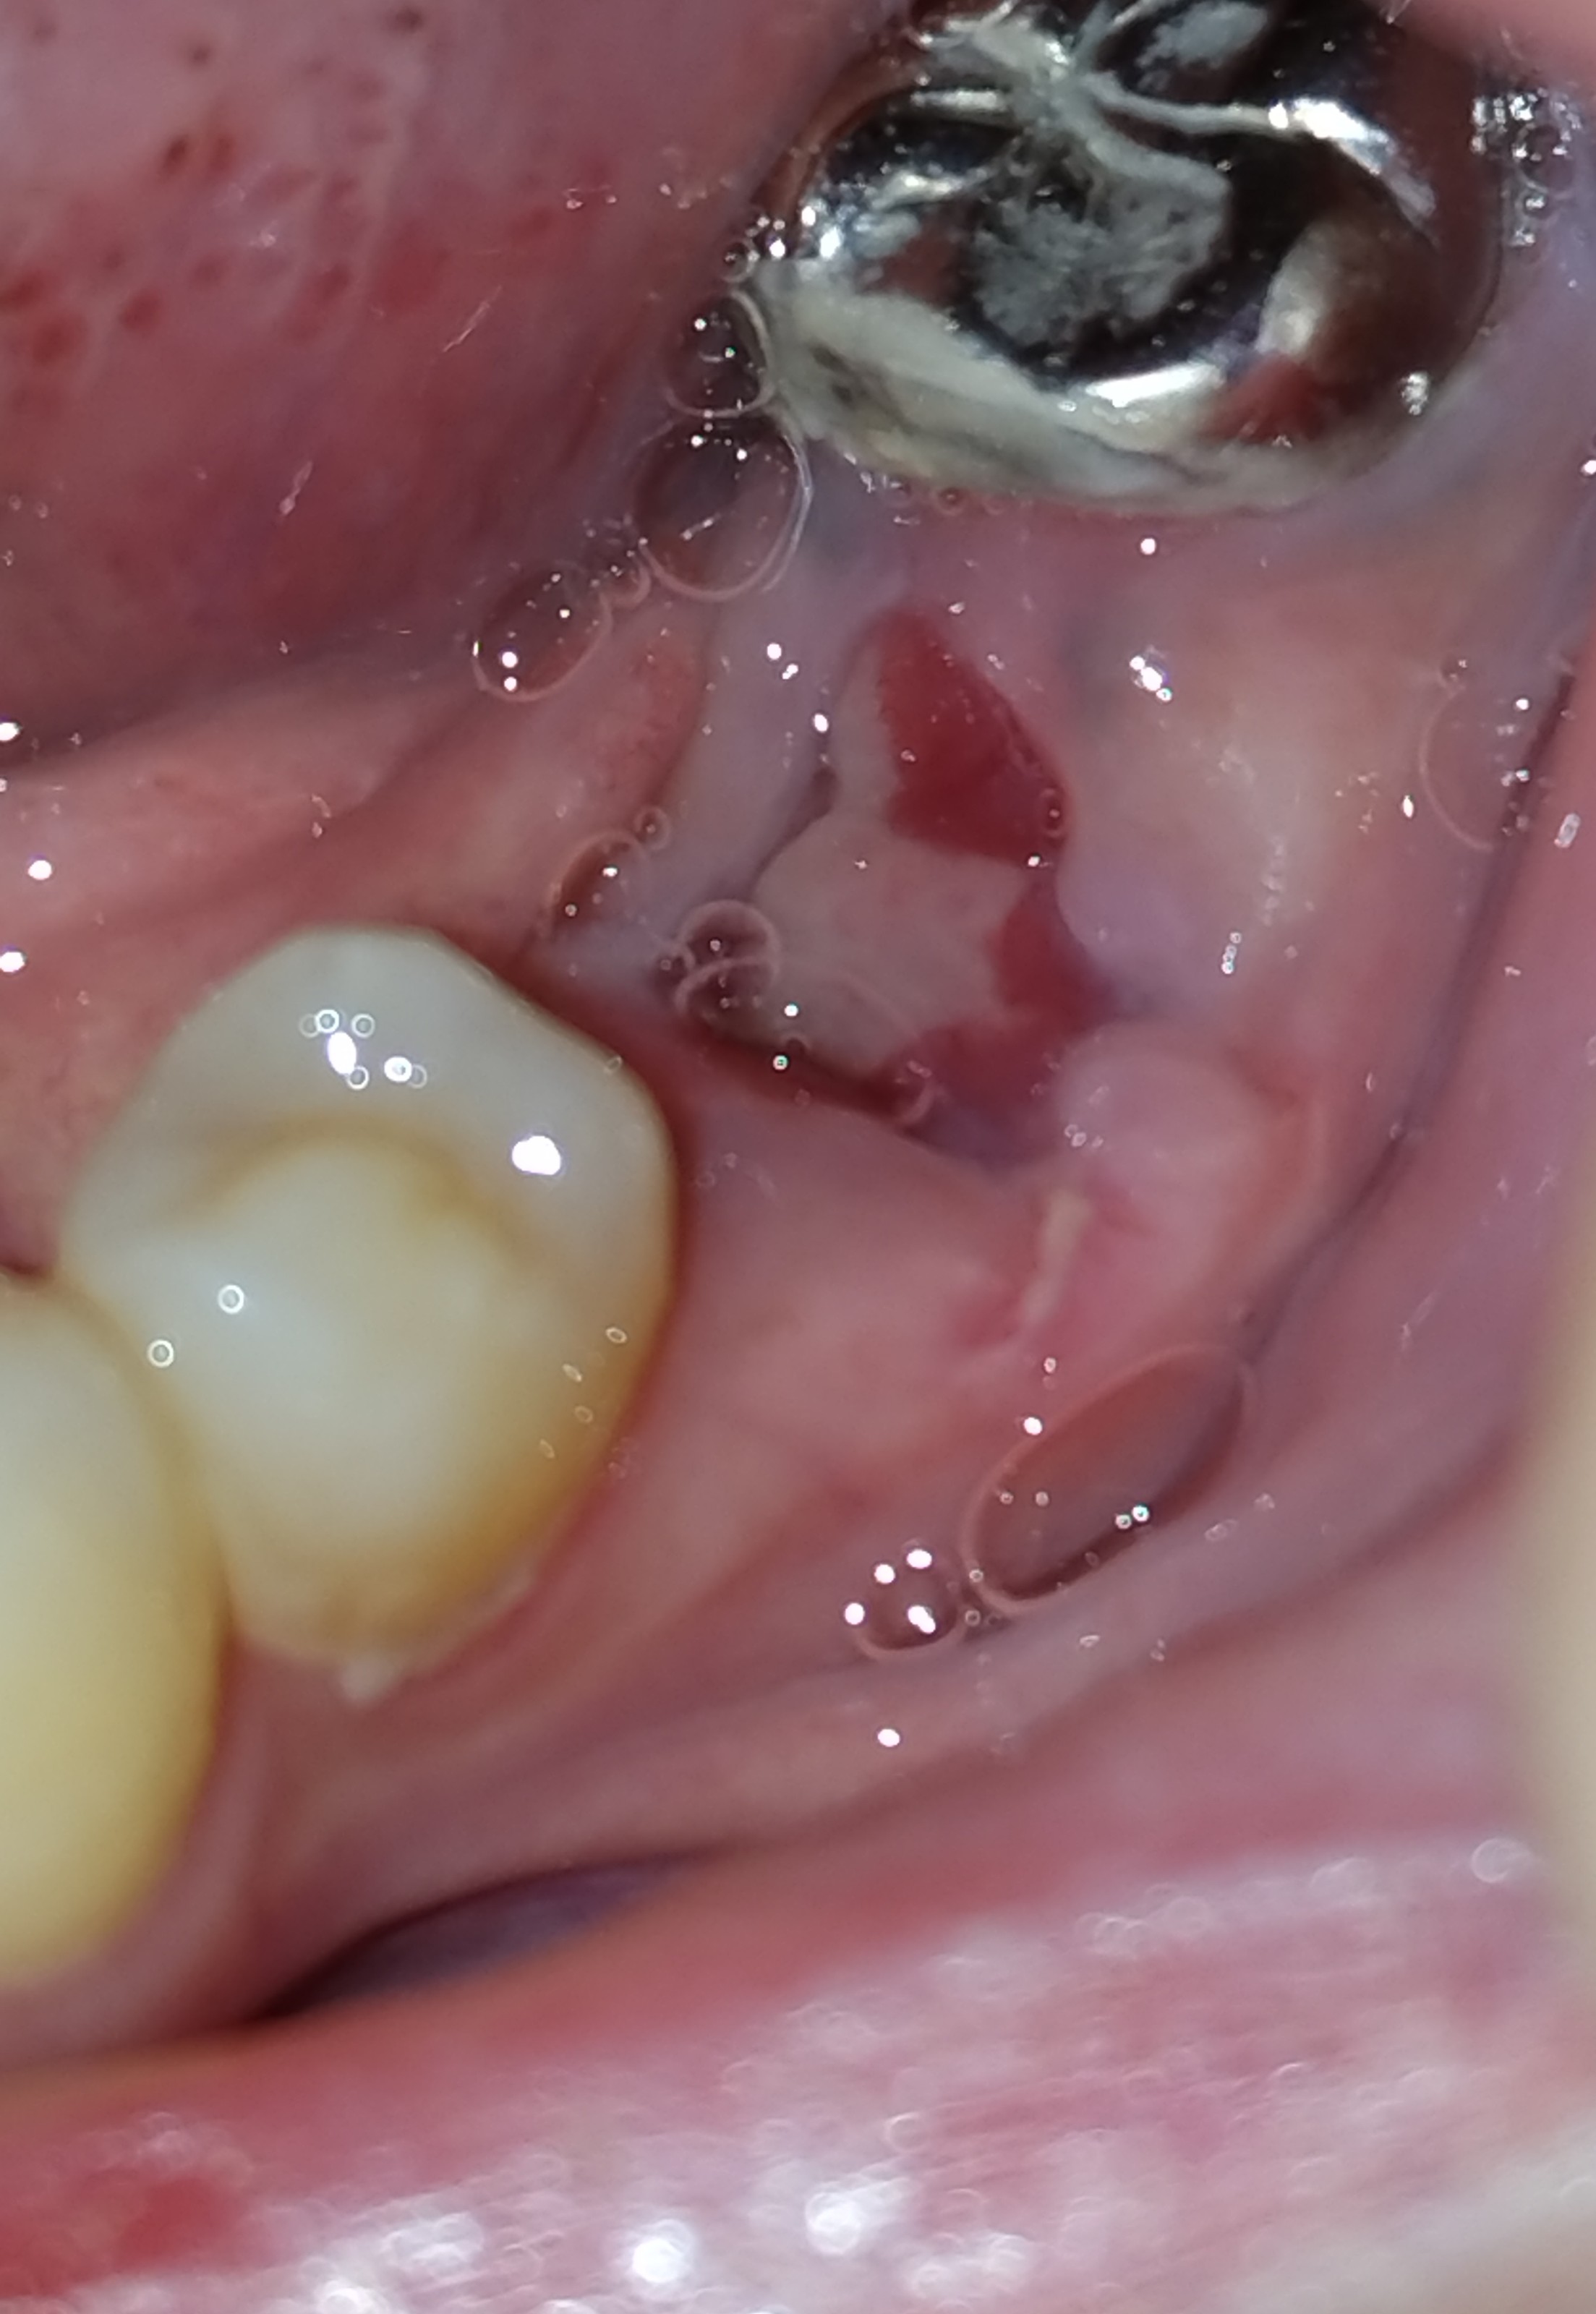

根尖性歯周炎になり、破折が原因で左下6番を抜歯しました。

あごに腫れを感じたまま抜歯を終えましたが、12日経った今もあごの辺りに異物感(つっぱる感じ)があります。